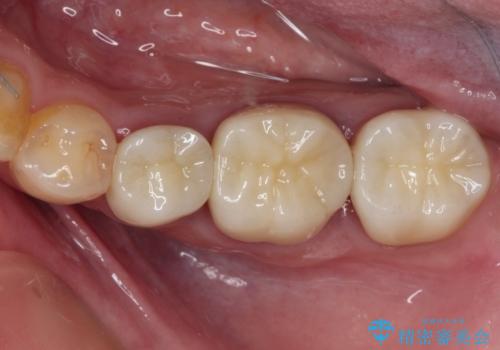

まだ銀歯が残っていますが、大きく目立つ銀歯をセラミックに置き換えることができ、人前で口を開けることを気にしなくなりました。

補綴治療中の後戻り対策をしっかりと行ったことで、歯列全体をきれいに整えることができました。